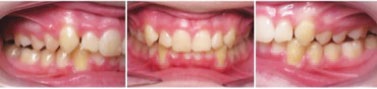

PATIENT INFORMATION:

• 14-year-old boy.

• Chief concern: overbite and crowding.

• Orthodontic diagnosis:

• Right side: Class II molar and canine (moderate).

• Left side: Class II molar and canine (severe).

• Overbite: severe deep bite.

• Upper arch: moderate crowding, with retroclined incisors.

• Lower arch: moderate crowding.

Figs. 3a-g: Initial records.